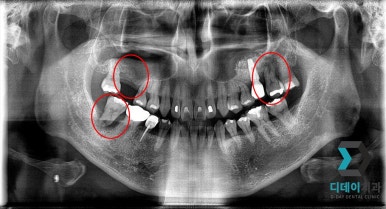

<전 2022-02-23>

<후 2022-10-14>